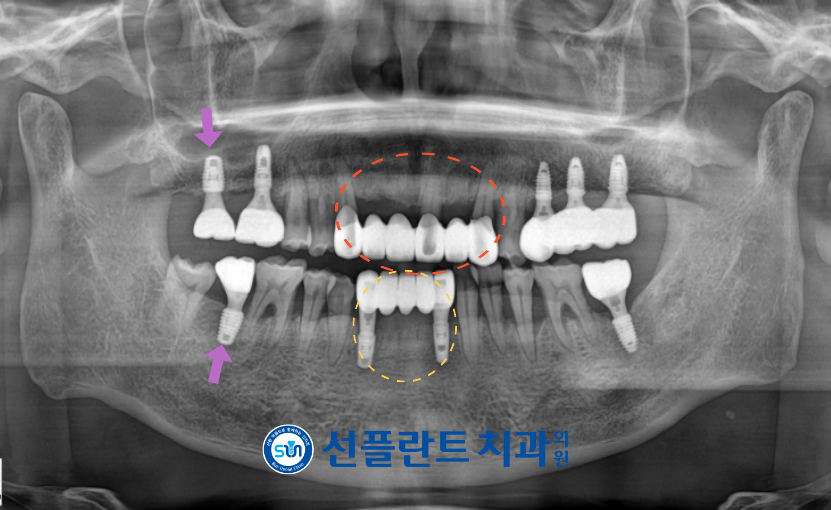

모든 치료가 마무리된

구강 내 사진과 파노라마 사진인데요.

처음 내원하셨을 때는

치주가 많이 좋지 않아

붉고 검 했던 치주가

장기간의 치주 치료를 통해

치주가 안정된 상태에서

보철이 진행되었다 보니

주변 치아와 앞니 보철의 색상이 조화롭고

균일화된 것을 확인할 수 있었는데요.

환자분께서도 앞니 색상이 고르게 정리되고

모양도 자연스러워진 모습에

심미성이 높아져 만족해하셨으며,

임플란트를 통한 어금니 기능 개선으로

양측 저작이 편안하게 되어

만족해하셨습니다.

전 > 후

초진: 2024.12.19종결: 2025.07.08